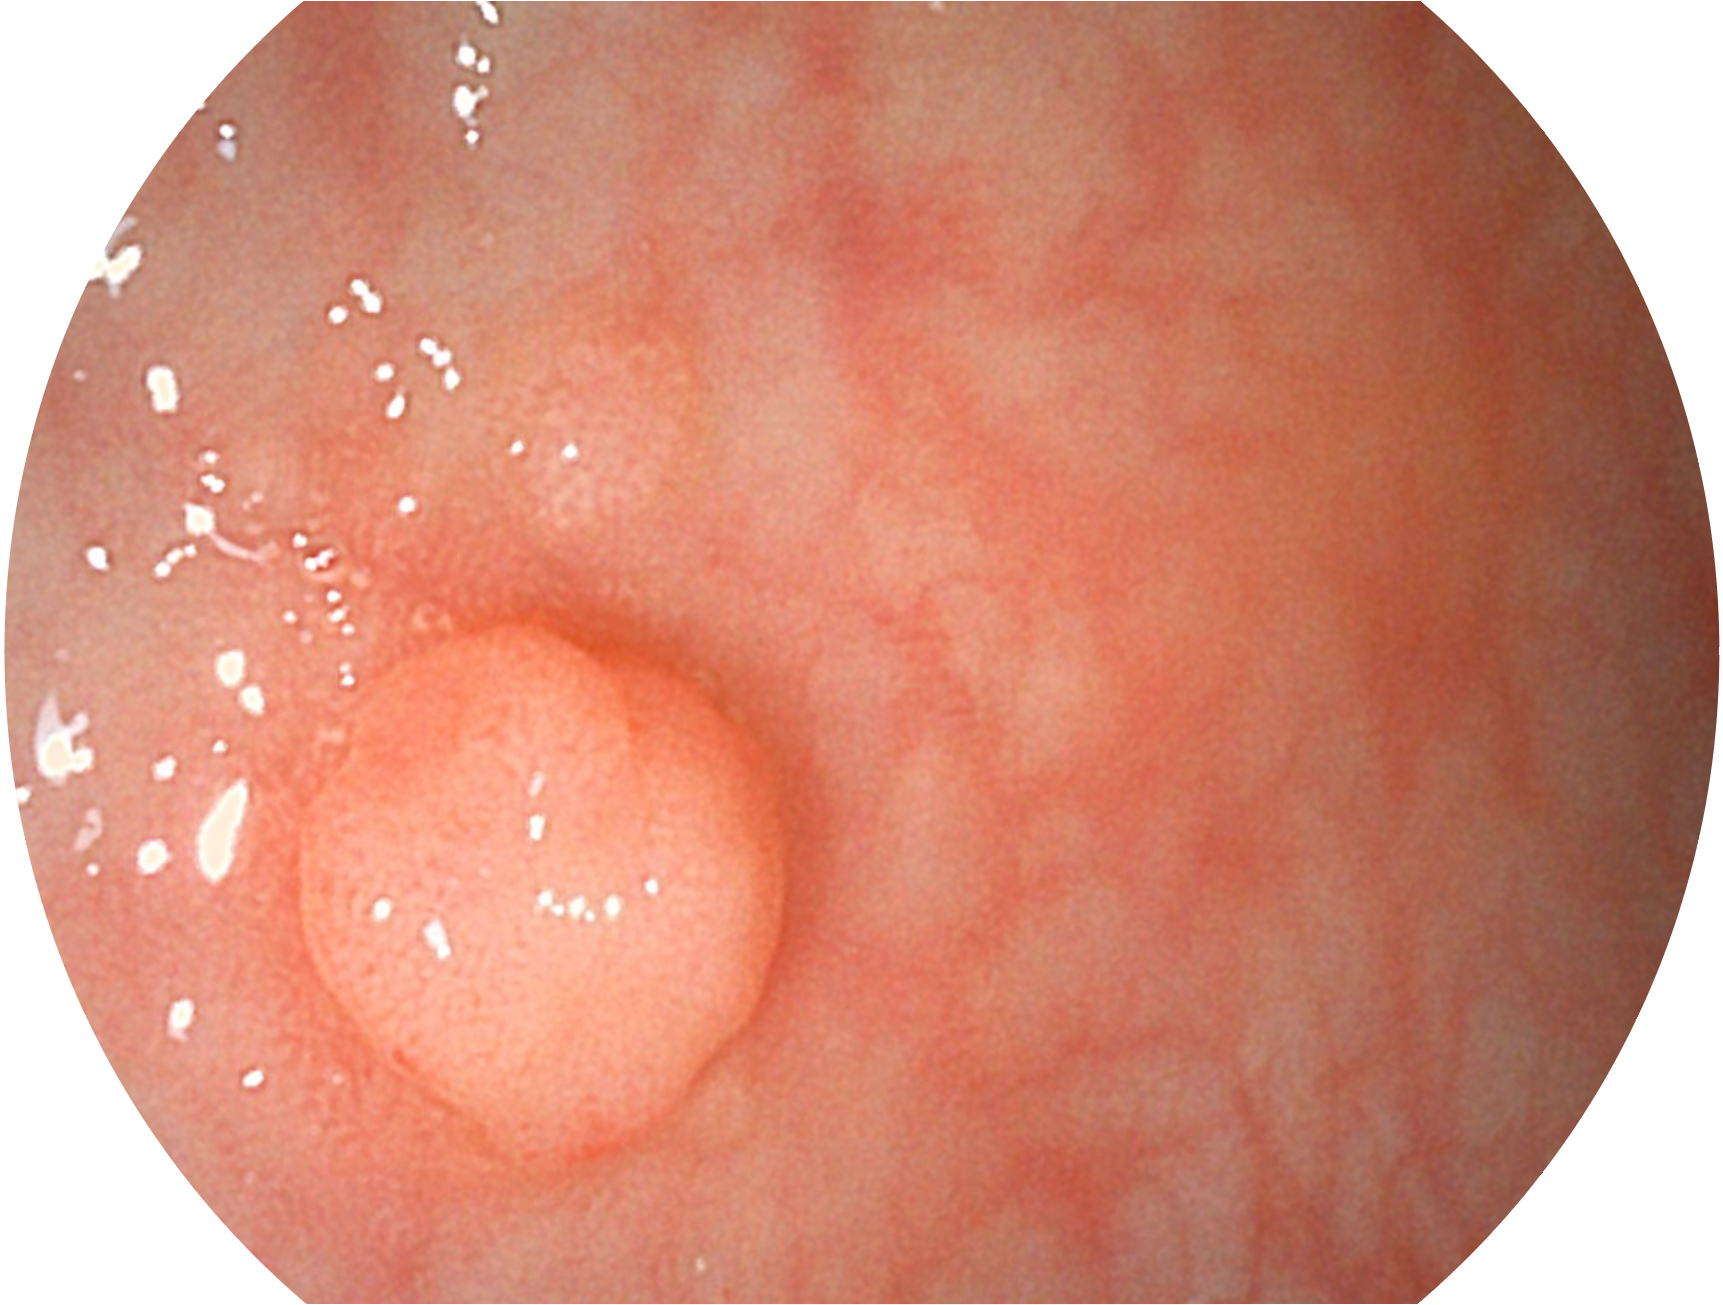

乐玩lewin国际新开发的内镜染色技术,主要是基于多波长LED 光源的开发,VLS-55Q 四波长LED 光源是由四个不同颜色的LED光按照相应照明模式所规定的特定发光比例进行合束后形成,合束后形成的照明光的光谱由红光、绿光、蓝光及蓝紫光这四个不同的波段范围构成。具有更高光谱自由度,通过光谱比例的控制,实现了聚谱成像技术,英文全称为“Spectral Focused Imaging, SFI”,缩写为“SFI”和光电复合染色成像技术,英文全称为“Versatile Intelligent Staining Technology, VIST”,缩写为“VIST”。